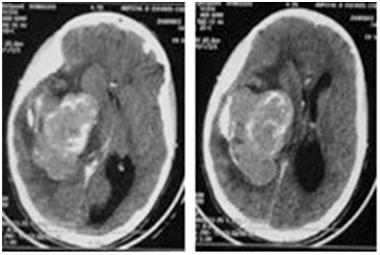

A 17years old female, presented with increasing intracranial pressure syndrome, severe headache, vomiting, and papillary oedema grade1. The patient was without any sensory or motor deficit. The CT and MRI shows a huge intraventricular lesion located in the occipital Horne of the right lateral ventricle (Figure 1). The patient underwent a ventricular shunting, and the tumor was excised in a second time. The removal was complete using a temporo parietal approach, and the post operative status was stable, with improvement of the headache. The histological exam indicates a fibroblastic meningioma (Figure 2).

Figure 2 The Histopathologic slide that confirms the diagnosis of meningioma.